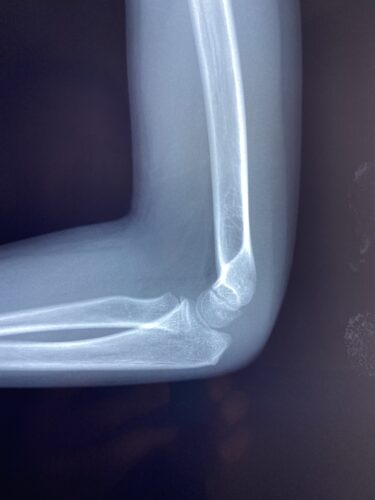

春日部市市民活動センター(肘関節脱臼)

肘関節前方脱臼の1症例について